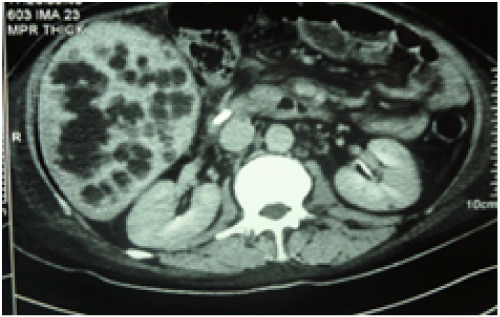

Figure 2: A patient with HAT and multiple hepatic abscesses managed with stenting of HAT and pigtail and antibiotics for abscesses

View Figure 2